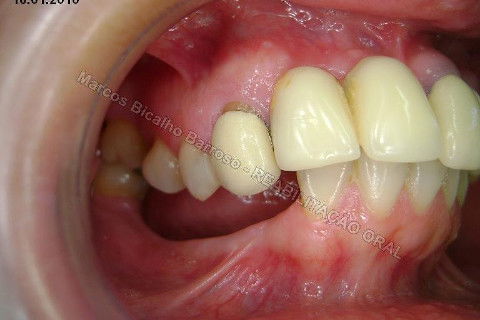

Paciente sexo feminino, 40 anos, queixava-se da situação da PPR superior, sem estabilidade, fraturas constantes nos dentes instalados. Sua vontade era resolver somente o problema da arcada superior, por questões financeiras. Logo no exame clínico inicial verifiquei a necessidade da reabiltiação inferior, pois este caso consistia em desarmonia oclusal severa, principalmente pela extrusão dos elementos 13,14 e 15 devido ausência de várias unidades inferiores. A proposta aceita pela paciente foi a instalação de 5 implantes na mandíbula + 5 implantes na maxila + tratamento endodôntico, osteoplastia e gengivoplastia nos dentes extruídos, incluindo núcleos metálicos e coroas em metalocerâmica (13,14,15). As coroas sobre implantes serão incialmente provisórias em resina fotopolimerizável e posteriormente metalocerâmica, de acordo com as possibilidades da paciente. Os procedimentos nos elementos extruídos serão apresentados em momento oportuno.